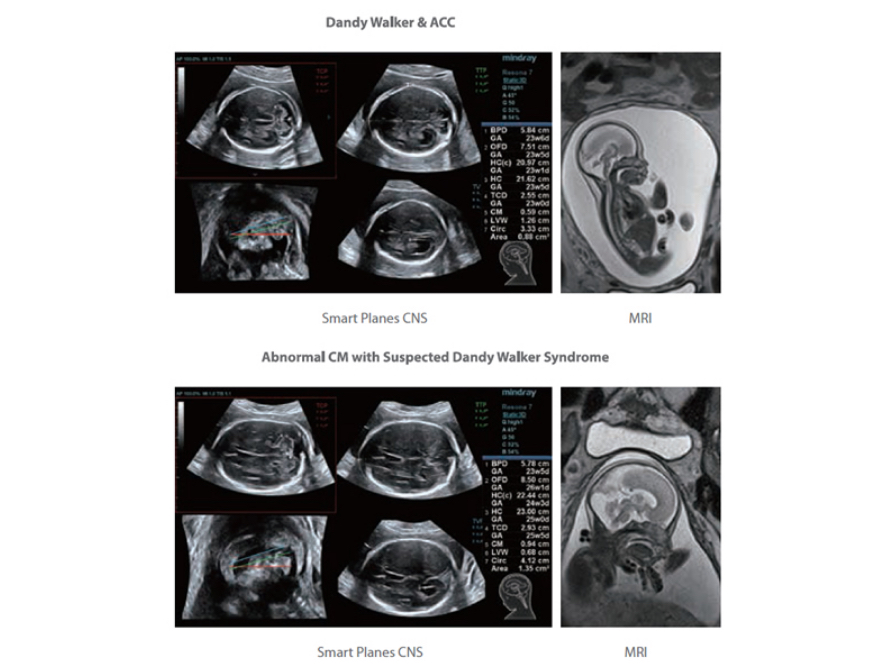

Mindray’s exclusive pioneering technology positions the Resona 6 as the industry’s first ultrasound system to allow fully automatic and accurate detection of the most significant planes and frequently used measurements of fetal CNS, leading to intelligent diagnosis, improved throughput, and reduced user dependency.

Smart Planes CNS provides a user-friendly tool that greatly improves scanning efficiency through increased accuracy coupled with automated operation. With a simple button click on a 3D fetal brain volume image, the standard CNS scanning planes (MSP, TCP, TTP and TVP) and a range of related anatomical measurements (BPD, HC, OFD, TCD, CM and LVW) are obtained immediately.